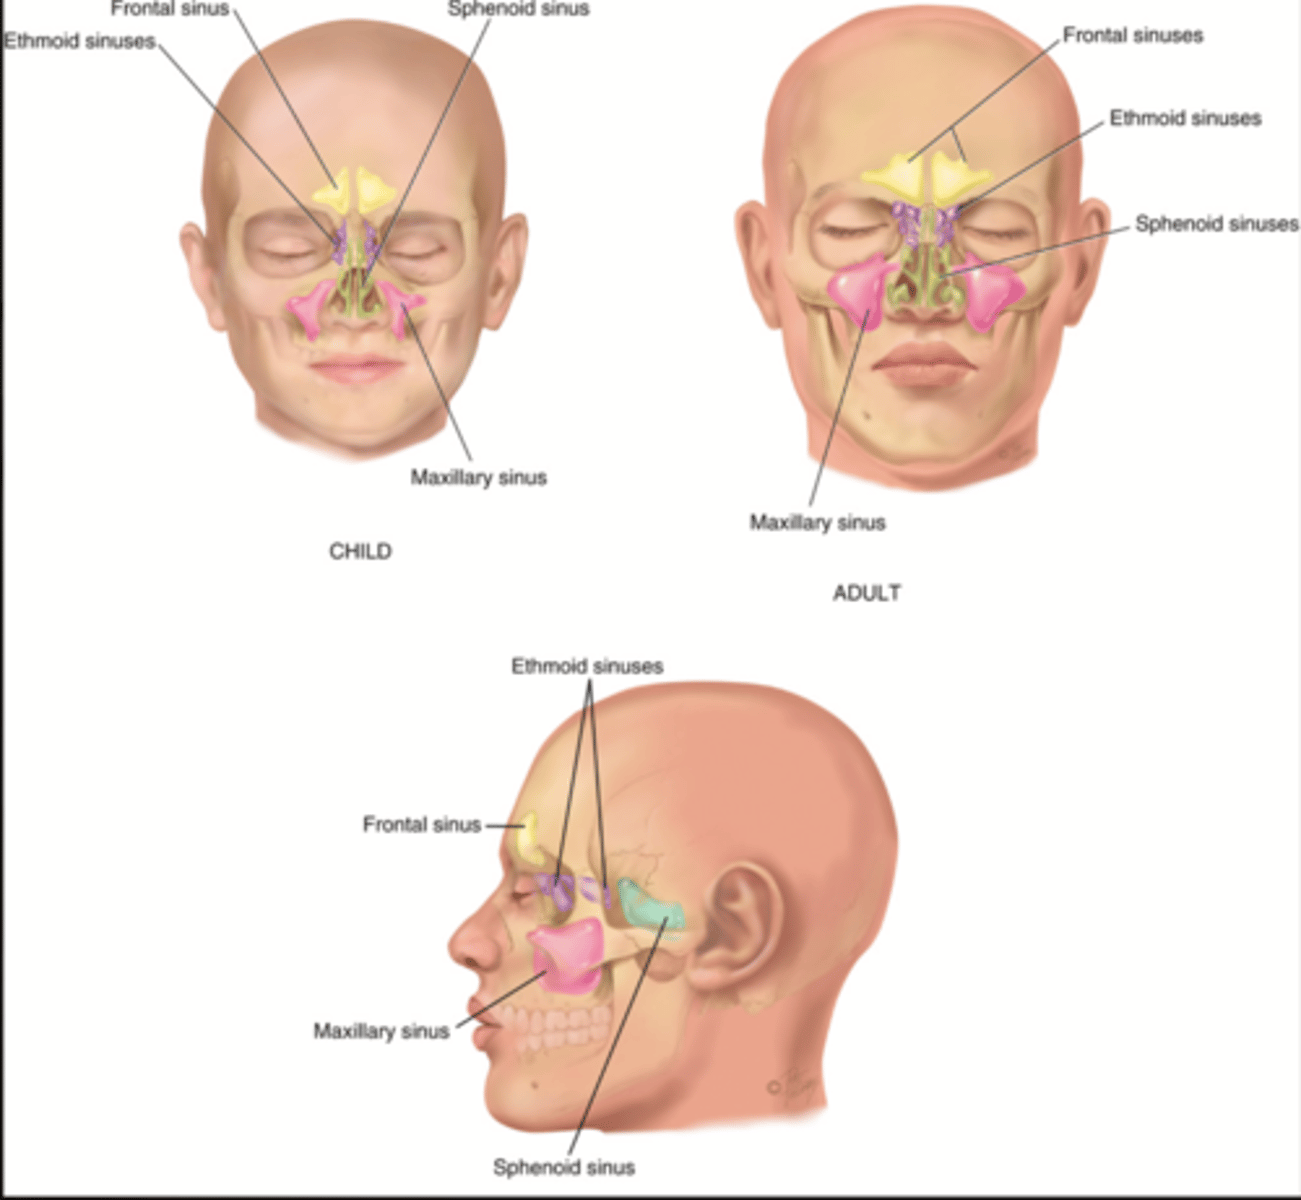

Paranasal Sinuses

- Frontal

- Ethmoid

- Sphenoid

- Maxillary

Frontal Sinus

Cavity within the frontal bone (yellow)

Ethmoid Sinus

Mucosa lined air spaces located above the sphenoid sinus and below the frontal sinus (purple)

Sphenoid Sinus

Sinus above and behind the nose (green)

Maxillary Sinus

Sinus on either side of the nasal cavity below the eyes (pink)